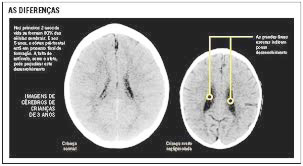

Assim, como é possível observar, diferentes variáveis podem influenciar se duas pessoas irão se apaixonar ou não. Ainda que os resultados de variados estudos mostrem que o Amor Romântico seja quase universal no mundo, nós não podemos categoricamente concluir que cada pessoa irá se apaixonar alguma vez na vida. Estudos também nos revelam que, embora o Amor Romântico possa ser controlado por algumas variáveis culturais, ele nunca será inteiramente suprimido. Não é muito claro que as pessoas se apaixonam mais frequentemente quando sua sociedade desaprova o Amor Romântico, mas é plenamente possível que as pessoas se apaixonem mais ou menos frequentemente dependendo da organização social de sua cultura e ideologia. Assim considerando, a ênfase cultural dada a cada uma dessas variáveis pode fazer a diferença. Mas, a despeito da importância, do papel, das variáveis culturais, ambientais (sociais, educacionais, econômicas, entre outras) sobre o amor, particularmente sobre o amor romântico, podemos nos perguntar: Onde está no cérebro o Amor? O amor romântico, onde está? Acevedo (a qual tive a satisfação de conhecer na UCSB-USA) e colaboradores, num estudo intitulado “Neural correlates of long-term intense romantic Love”, publicado na revista SCAN (2012) 7,145-159, procuraram desvendar os correlatos neurais do amor romântico intenso e de longo prazo usando a técnica de imageamento de ressonância magnética funcional (fMRI, na sigla em inglês). Para isso ela e membros da sua equipe requereram que dez mulheres e 7 homens, casados há em média 21,4 anos, fossem submetidos às imagens de fMRI enquanto visualizavam imagens faciais de seus parceiros.

As imagens de controle incluíam um conhecido altamente familiar; um amigo próximo e de longa data; e uma pessoa pouco familiar. Efeitos específicos para o parceiro intensamente amado e de longo prazo foram encontrados em: (i) áreas do sistema de recompensa rico em dopamina e dos gânglios da base, como a área tegmental ventral (VTA, na sigla em inglês) e o corpo estriado dorsal. Tais dados foram consistentes com resultados de estudos de amor romântico em estágio inicial; e (ii) várias regiões implicadas no apego materno, como o globo pálido (GP, também chamado de paleoestriado, é uma estrutura subcortical do cérebro que integra o telencéfalo), substância negra, núcleo da rafe, tálamo, córtex insular, cingulado anterior e cingulado posterior.

Correlações de atividade neural em regiões de interesse com os escores de questionários amplamente usados na área mostraram: (i) respostas VTA e caudadas correlacionadas com escores de amor romântico e inclusão de outros (valorização de outros) no ego (self); (ii) respostas do GP correlacionadas com pontuações de amor baseadas na amizade; (iii) respostas do hipotálamo e do hipocampo posterior correlacionadas com frequência sexual; e (iv) respostas no núcleo caudado, septo/fórnice, cingulado posterior e hipocampo posterior correlacionadas com escores de obsessão obtido nos questionários. No geral, os resultados sugerem que, para alguns indivíduos, o valor da recompensa associado a um parceiro de longo prazo pode ser sustentado, semelhante ao novo amor, mas também envolve sistemas cerebrais implicados no apego e na ligação entre pares.

Em suma, os dados de Bianca Acevedo e equipe (2012) mostraram que as respostas baseadas nas imagens de um parceiro amado e de longa data foram associadas aos sistemas cerebrais que foram identificados como sendo tão importantes como o ‘gostar’ das recompensas primárias. Além disso, os resultados mostraram ativação do GP posterior e insular do córtex em função de pontuações de amor baseadas na amizade. A ativação dessas regiões no contexto atual sugere aspectos do “gostar “ou “prazer” relacionados ao relacionamento com um dado parceiro. Portanto, o amor romântico, de alguma forma, ativa áreas muito especiais em nosso misterioso e enigmático cérebro. Ao fim e ao cabo, talvez, Freud tenha tido, ou mesmo, tenha razão mesmo numa sociedade complexa e com pressa.